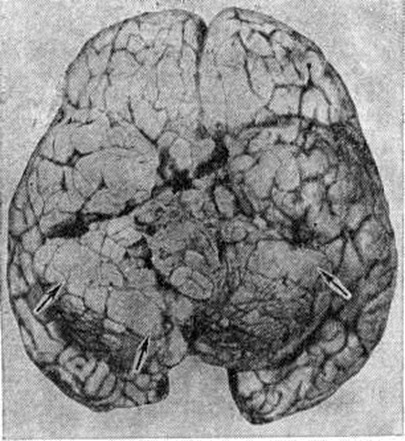

Рис. 2.

Макропрепарат головного мозга (базальная поверхность) с метастазами медуллобластомы в мягкую оболочку (стрелками обозначены наиболее крупные метастатические узлы).

Макроскопически Медуллобластома имеет вид мягкого узла сероватого или серовато-розового цвета, довольно чётко отграниченного от окружающей ткани. Микроскопически опухоль состоит из густо расположенных недифференцированных клеток, образующих иногда своеобразные ритмические структуры в виде правильных или беспорядочных рядов, которые сравнивают с грядами и колоннами (рисунок 1). Особенно характерны микроскопические структуры в виде так называемый розеток, образованных кольцевидно расположенными опухолевыми клетками, отростки которых сходятся в центре розетки. Опухолевые клетки умеренно полиморфны, с многочисленными митозами. Наряду с гиперхромными мелкими округлыми ядрами в клетках Медуллобластома встречаются овальные и вытянуто-овальные, удлинённые, а также более крупные светлые округло-овальные ядра с чётким ядрышком. Строма опухоли скудная, с небольшим количеством преимущественно мелких, тонкостенных сосудов. Очаги некроза и кисты не типичны. Рост опухоли инфильтративный с прорастанием прилежащей ткани и мягкой оболочки мозга, нередко с вторичным врастанием из оболочки в подлежащую ткань. Медуллобластома метастазирует главным образом по ликворным пространствам, в мягкую оболочку и эпендиму желудочков мозга, в которых определяются плоские, сливающиеся между собой белесоватые узелки (рисунок 2), переходящие в диффузные разрастания. Иногда Медуллобластома даёт метастазы в лимф, узлы, кости, органы желудочно-кишечные тракта.